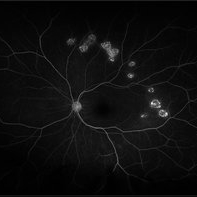

Disseminated Chorioretinitis With Unknown Etiology

Disseminated Chorioretinitis With Unknown Etiology

Apr 5 2018 by Kim Barrett

Ultra-wide field fluorescein angiogram of a 31-year-old female with intermittent pain in her left eye. Her condition has been managed in Liberia until recently when she moved to the United States. She suffers from multiple modalities including central retinal artery occlusion, posterior synechiae of the iris, interstitial keratitis, disseminated chorioretinitis, as well as HIV. An infectious cause is high on the differential in light of her HIV status. DDx: hypertensive crisis, an embolism (? IV drug use), coagulopathy, trauma, infectious. Blood work was normal. Her current vision is 20/30 right eye and 20/400 left eye.

Photographer: Kim Barrett, COA

Imaging device: Optos

Condition/keywords: central retinal artery occlusion (CRAO), chorioretinal scar, ciliary artery sparring, disseminated chorioretinitis, HIV, left eye, optic atrophy, staining